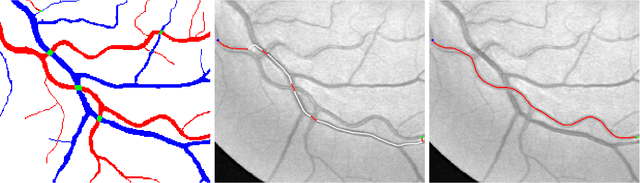

In this paper, we propose a new minimal path model for minimally interactive retinal vessel centerline extraction. The main contribution lies at the construction of a novel coherence-penalized Riemannian metric in a lifted space, dependently of the local geometry of tubularity and an external scalar-valued reference feature map. The globally minimizing curves associated to the proposed metric favour to pass through a set of retinal vessel segments with low variations of the feature map, thus can avoid the short branches combination problem and shortcut problem, commonly suffered by the existing minimal path models in the application of retinal imaging. We validate our model on a series of retinal vessel patches obtained from the DRIVE and IOSTAR datasets, showing that our model indeed get promising results.